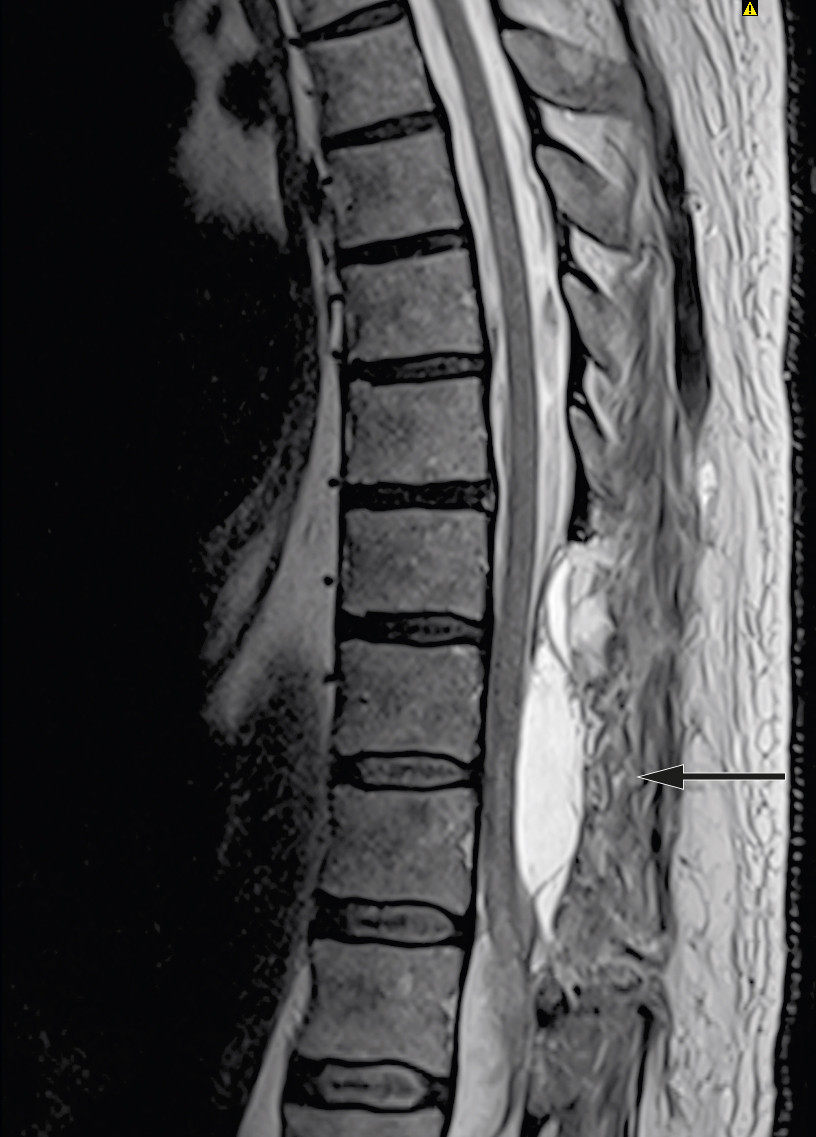

Examination upon admission showed blood pressure 146/68 mm Hg, heart rate 70 beats/min, Hb 15.4 g/dl (reference range 13.4–17.0 g/dl), platelets 241 ∙ 109/l (145–390 ∙ 109/l), creatinine 72 µmol/l (60–105 µmol/l) and Quick INR 2.6 (within the therapeutic range of 2–3). MRI revealed an intraspinal subdural haematoma at levels Th9–L1 with dislocation of the spinal cord and medullary cone (Figure 1). CT angiography showed no evidence of vascular malformation or arteriovenous fistula. Based on interpretation of an acute MRI, the patient was given phytomenadione (Konakion, 10 mg) and prothrombin complex concentrate (Octaplex, 2 500 IU), dosed according to the recommendations of the Neurology-Norwegian Electronic Medical Handbook ('NevroNEL') (4), to avoid further haemorrhaging.

The patient was signed up for emergency surgery under general anaesthesia. The knee-elbow position was used, along with X-ray imaging, midline incision and three-level laminectomy. No epidural haematoma was seen during the surgery, but the blue discoloured dura mater was opened. The subdural haematoma was gently evacuated, and there was no major source of bleeding or difficulty in achieving haemostasis. The spinal cord showed bluish discolouration, and significant subarachnoid and intramedullary haemorrhage was suspected. Closure was then performed under good haemostasis. Postoperative MRI showed a reduced subdural haematoma at laminectomised levels Th9–11, unchanged subdural haematoma at level Th12, new intramedullary signal changes at Th10–L1, and subarachnoid blood caudal to Th12 (Figure 2).